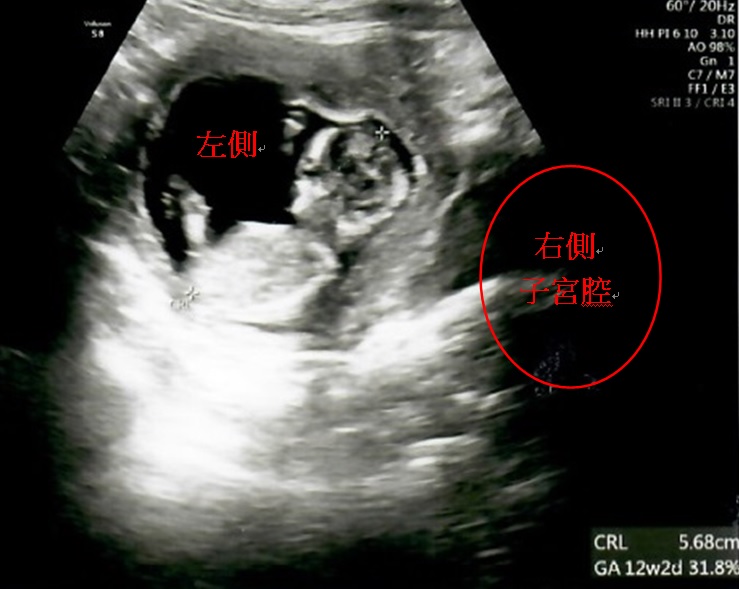

▲胚胎植入右側子宮腔的位置 ▲胎兒在產婦右側子宮腔內著床發育

因著求子心切,加上政府推出擴大試管補助方案,讓陳小姐和先生決定直接採用試管療程,不想再浪費時間嘗試自然受孕,希望能儘快抱到孩子。於是,李茂盛院長幫王小姐進行1次取卵手術共取出9顆卵子,在受精後得到3顆囊胚,經過「AI人工智慧試管技術」、「胚胎影像即時監控系統(T/L)」,從中找出發育最好的1顆第5天囊胚,植入右側的子宮腔內,囊胚即順利著床發育,直到孕期34週又2天時,陳小姐自然產下重達2460公克的健康男寶。